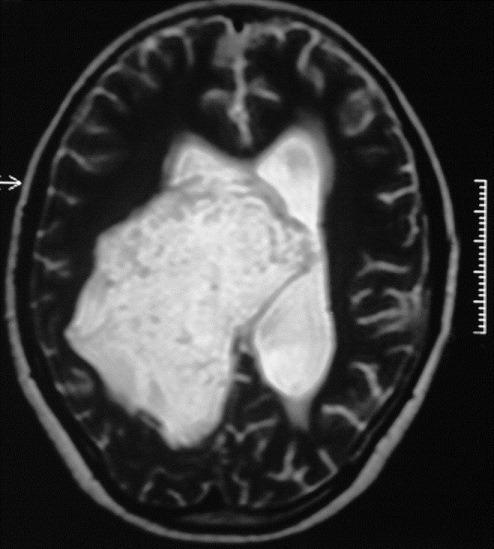

一名脑积水儿童的侧脑室内表皮样囊肿。

Lateral intraventricular epidermoid in a child with hydrocephalus.

Lateral intraventricular tumors are uncommon. They grow linearly rather than exponentially and hence are slow-growing lesions without causing mass effects and hydrocephalus. We report a rare case of large bulky right intraventricular epidermoid tumor in a child. This tumor was associated with mass effect on the surrounding structures and hydrocephalus.

摘要